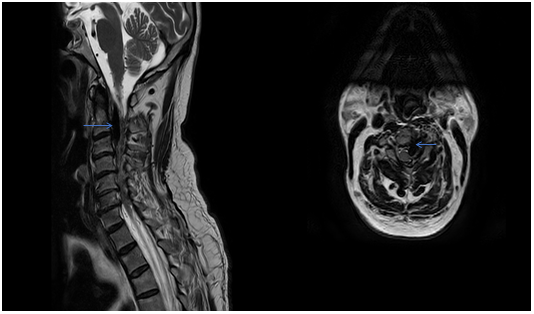

A Contrast Computerized Tomography (CT) scan showed a large vascular malformation around the craniovertebral junction extending from C0 to C3 fed extradurally and extrevertebrally (Figure 2). The patient was explained the nature of the disease as well as the modalities of management. He was then taken up for a Digital Subtraction Angiographic study of the lesion with a concomitant glue/ onyx injection. The angiogram showed a large high cervical epidural AV fistula (EDAVF) being fed by branches from bilateral vertebral, ascending pharyngeal and deep cervical arteries, left more than right (Figure 3). The EDAVF however was exclusively present on the left side. The right sided feeders seemed to be miniscule and to contribute minimally to the flow. The patient was also seen to have a persistent Left Trigeminal artery which augmented flow from the left Internal carotid artery into the Left Vertebral artery. This presented us with an excellent setting for Endovascular treatment for the vertebral feeders.

Figure 3 Microcatheter placed at the mouth of the feeder arising from the V2 segment of the ipsilateral vertebral artery.

The patient was then administered general anesthetic. IV heparin of approximately 1000U was administered every hour further on and a Heparin flush was connected to the femoral sheath. The 5F short sheath was then exchanged for a Neuron Max 088 Sheath which was placed under fluoroscopic guidance into the left proximal subclavian artery. A 5F Navien catheter was then advanced into the Left Vertebral Artery railroaded on a 035 guidewire. Over this the Neuron Max catheter was moved co-axially into the proximal vertebral artery as well. An Echelon Microcatheter was then taken over the 014 Traxcess microwire and feeders from the distal V2 segment of the vertebral artery were selectively catheterized and visualized. The large lateral feeder which was significantly dilated was chosen for onyx injection (Figure 4). DMSO was injected to fill the dead space of the microcatheter and Onyx was injected under multiple blank roadmap guidance into the feeder to fill the EDAVF sac partially. Reflux into the main vertebral artery was noted, after which the injection of the onyx was stopped. Post injection films showed complete obliteration of the feeders from the vertebral artery (Figure 5).

Figure 4 Injection of the large lateral feeder showing filling of the fistula.